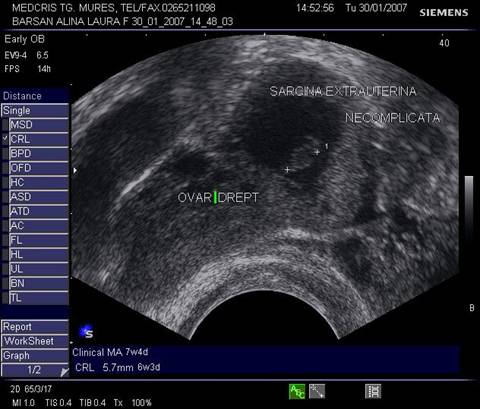

Fig nr 52

Langa ovarul drept ( cu sageata lunga ) se observa o formatiune ovalara cu ecou

hipoecogen central, sarcina extrauterina la 5 sapt. si 3 zile de amenoree ( doua sageti )